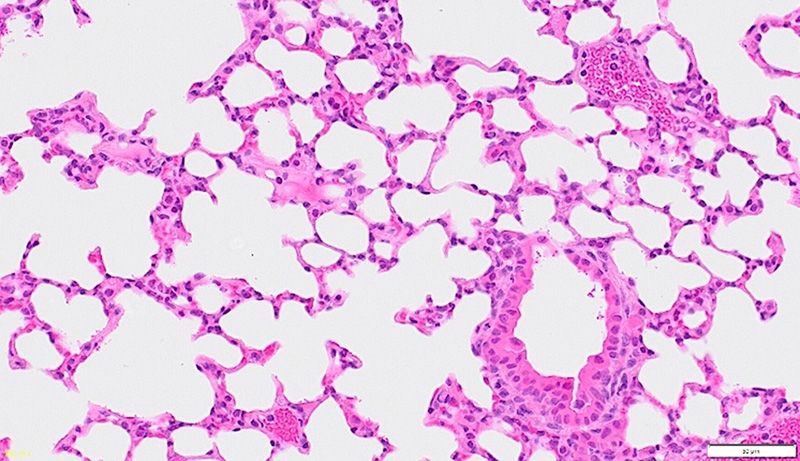

本検証では、透明化処理を行ったマウス肺組織を用いて、透明化後の組織に対する病理染色の適用性を評価しました。

透明化処理を行った組織は再度パラフィン包埋を行い、薄切切片を作製した後、スタンダードプロトコルに従ってHE染色およびMT染色を実施しています。

透明化処理を行ったマウス肺組織を再パラフィン包埋後に薄切し、スタンダードプロトコルでHE染色を実施しました。肺胞構造および肺胞隔壁が良好に観察され、細胞核も明瞭に確認されました。また、管腔構造も認められ、肺組織としての基本的な形態が維持されている様子が確認されました。

透明化処理後においても、再パラフィン包埋および各種染色により、肺組織の基本的な組織構造および結合組織成分が良好に保持されていることが確認されました。

ROCCITのプロセスでは処理工程の一部に電気泳動プロセスが含まれますが、今回の観察結果からは、組織構造および染色性に関して顕著な変化は認められませんでした。 これらの結果から、透明化処理後の組織においても、従来の病理染色と組み合わせた組織解析が可能であることが示唆されます。